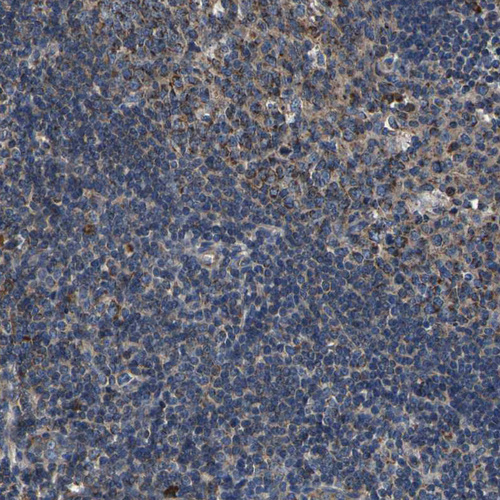

Immunohistochemistry analysis in human endometrium and tonsil tissues using HPA012285 antibody. Corresponding INPP5A RNA-seq data are presented for the same tissues.